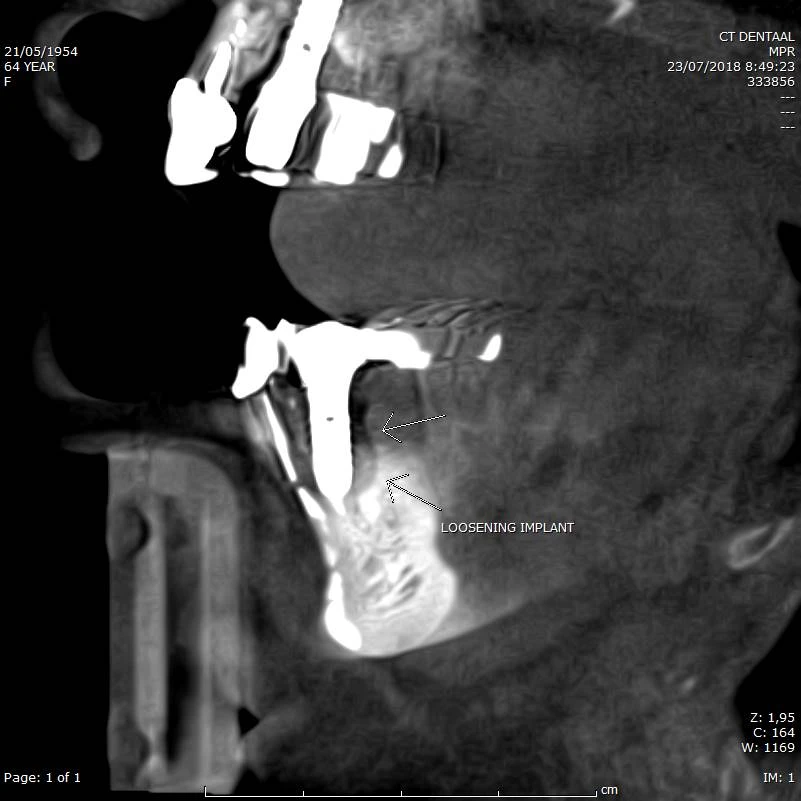

Mogelijks los zittend implant mandibulair

CBCT voorbeeld 3: loszittend implant

Sagittale doorsnede: loszittend implant in de mandibula